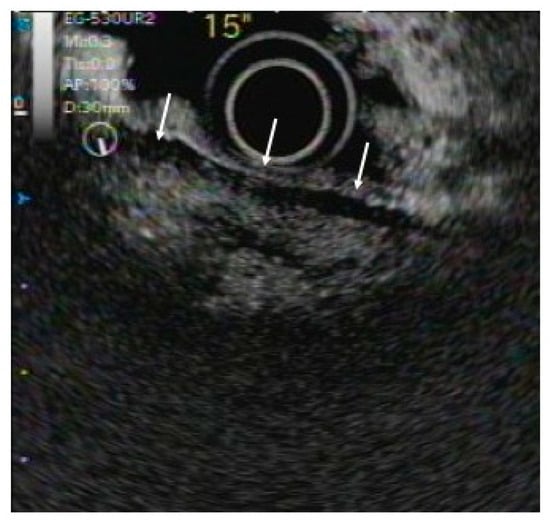

3.2. IDUS

- Naitoh, I.; Nakazawa, T.; Ohara, H.; Ando, T.; Hayashi, K.; Tanaka, H.; Okumura, F.; Takahashi, S.; Joh, T. Endoscopic transpapillary intraductal ultrasonography and biopsy in the diagnosis of IgG4-related sclerosing cholangitis. J. Gastroenterol. 2009, 44, 1147–1155. [Google Scholar] [CrossRef]

- Kuwatani, M.; Kawakami, H.; Zen, Y.; Kawakubo, K.; Kudo, T.; Abe, Y.; Kubo, K.; Sakamoto, N. Difference from bile duct cancer and relationship between bile duct wall thickness and serum IgG/IgG4 levels in IgG4-related sclerosing cholangitis. Hepatogastroenterology 2014, 61, 1852–1856. [Google Scholar]